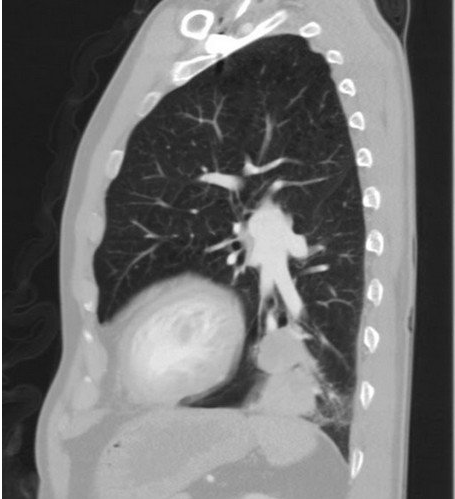

左圖:一位70多歲的男性病人,因有重度吸菸史、久咳不癒,到花蓮慈濟醫院求診,檢查發現疑似左肺惡性腫瘤。(鍾秉儒醫師提供)

一位70多歲的男性病人,因有重度吸菸史、久咳不癒,到花蓮慈濟醫院求診,檢查發現疑似左肺惡性腫瘤,經電腦斷層導引切片和全身正子檢查後,團隊診斷為第二期肺腺癌,經胸腔外科鍾秉儒醫師以達文西機械手臂輔助胸腔鏡手術切除左下肺葉,病人快速復原,在術後第二天觀察相關指數均無異常,即辦理出院。

鍾秉儒醫師指出,衛生福利部健保署自2023年3月起新增多項達文西手術給付,病人可減輕一大部分醫療費用;這位病人為肺腺癌症第二期,雖沒有淋巴轉移,但手術後復發率仍可高達3到4成,選擇達文西手術,可做更多淋巴廓清,一些文獻指出,可有效降低復發率。病人術後第一天移除引流管,第二天出院,目前口服抗腫瘤藥物,並定期門診追蹤,日常生活一切正常,跟手術前一樣。